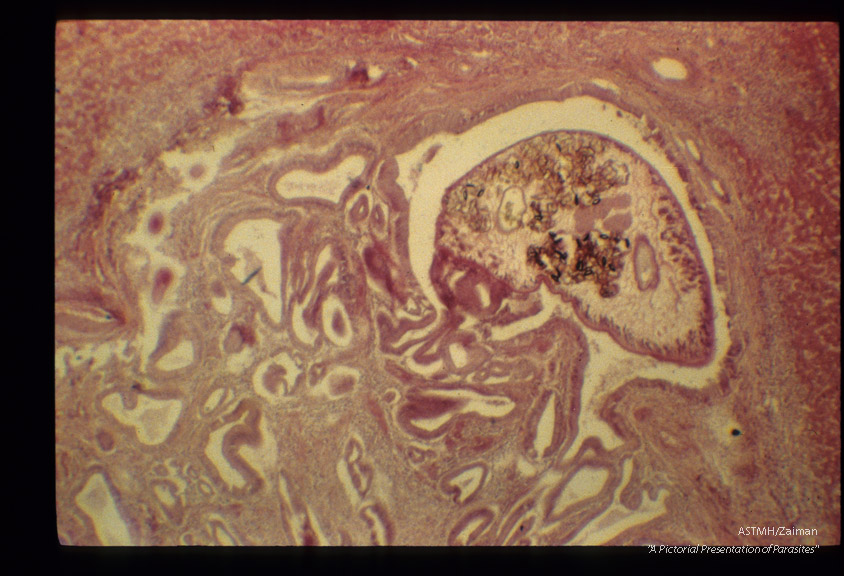

Adult in bile duct which shows marked hyperplasia of epithelium.

Clonorchis sinensis

Description: Adult in bile duct which shows marked hyperplasia of epithelium.